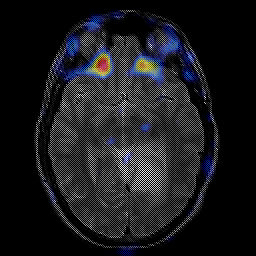

glioma overlay -- Slice #12

[Home][Help][Clinical] Slice 12